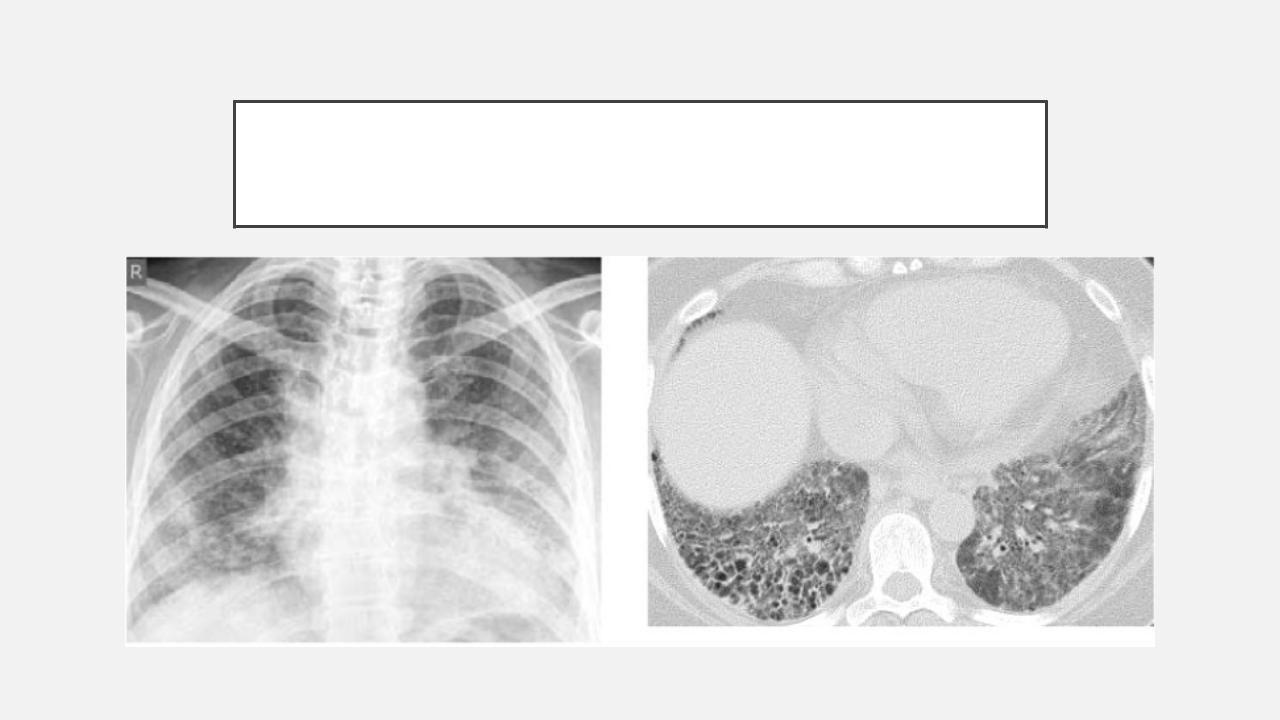

Острая внебольничная пневмония по МКБ-10: признаки и примеры